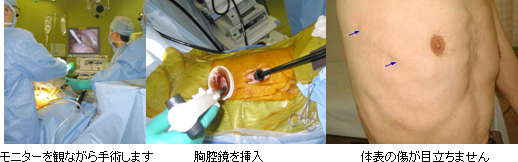

当院の肺がん手術は基本的に胸腔鏡下手術による低侵襲手術であり、手術創も小さく早期回復が期待できます。平成23年度の肺がん手術症例は80例でしたが、そのうち77例が胸腔鏡下手術(96%)で、3例が開胸手術(4%)でした。

1.5cm程度と6~8cm程度の2箇所の創から胸の中に胸腔鏡(内視鏡)を挿入した後、モニターを観ながら(テレビの画面に胸の中が映し出されます)行う手術です。痛みの原因となる胸壁の筋肉・神経の損傷が少なく、術後の創部痛が開胸手術に比べはるかに軽減されます。体表の傷が小さい低侵襲手術ですから、早期離床が可能で早期退院が期待できます。

胸腔内の高度な癒着や手技的が困難と判断された症例に対しては、6~8cm程度の創を12~15cm程度に延長・拡大して開胸手術を選択します。